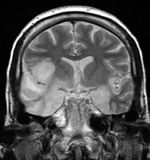

| Herpesviral encephalitis | A herpetic infection of the brain that is thought to be caused by the retrograde transmission of virus from a peripheral site on the face following HSV-1 reactivation, along the trigeminal nerve axon, to the brain. HSV is the most common cause of viral encephalitis. When infecting the brain, the virus shows a preference for the temporal lobe.[2]. | |